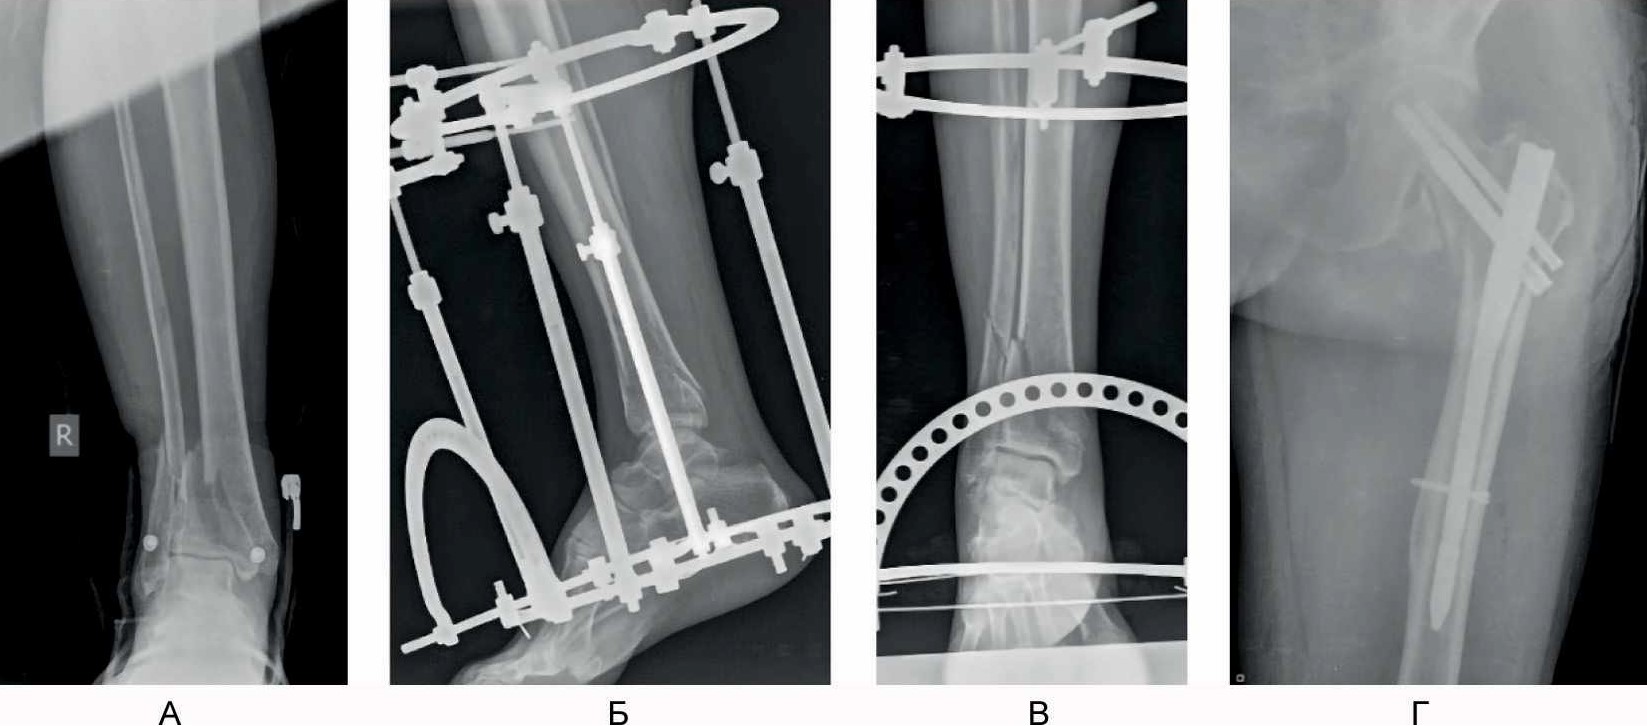

Положение отломков и имплантатов в ходе операции контролировали интраоперационной рентгеноскопией при помощи рентгеновского электронно-оптического преобразователя. Рентгенологический результат операции представлен на рис. 6.

Рис. 6. Рентгенограммы в боковой (А) и прямой (Б) проекциях после выполнения малоинвазивного накостного остеосинтеза нижней 1/3 большеберцовой кости.

Пациент осмотрен через 3 мес после операции. Он ходит с частичной опорой на оперированную конечность с тростью. Болевой синдром отсутствует. Тыльное сгибание и разгибание голеностопного сустава – в объеме 90–130°, функциональный результат по шкалам AOFAS и Neer [16, 21] составил 71 и 76 баллов соответственно (рис. 7).

Рис. 7. Результат оперативного лечения через 3 мес после вмешательства.

Руководствуясь изложенными соображениями, при предоперационном планировании остеосинтеза у нашего пациента Б., 66 лет, с переломом в области метаэпифиза правой большеберцовой кости и нижней трети диафиза малоберцовой кости мы постарались решить проблему латеральной стабильности с помощью установки опорной переднелатеральной пластины на большеберцовую кость, восстановив ее длину с помощью закрытой тракции в аппарате наружной фиксации (и этот момент мы считаем крайне важным, так как первичное восстановление осевых взаимоотношений и сохранение их в течении дооперационного периода, безусловно, облегчает репозиционные маневры в ходе окончательного остеосинтеза), с последующей установкой пластин через мини-доступы. Фиксация же малоберцовой кости из отдельных доступов в данном случае не потребовалась, так как цель ее остеосинтеза – устранение вальгусной деформации и латеральная стабильность – была решена остеосинтезом самой большеберцовой кости. Правомерность выбранной нами тактики в случае у нашего пациента была доказана клиническим и рентгенологическим сращением перелома большеберцовой кости, отсутствием при этом вторичного смещения отломков и хорошим функциональным результатом.

Контрольные рентгенограммы в прямой (А) и боковой (Б) проекции – определяется сращение перелома; В–Д – функциональный результат лечения.